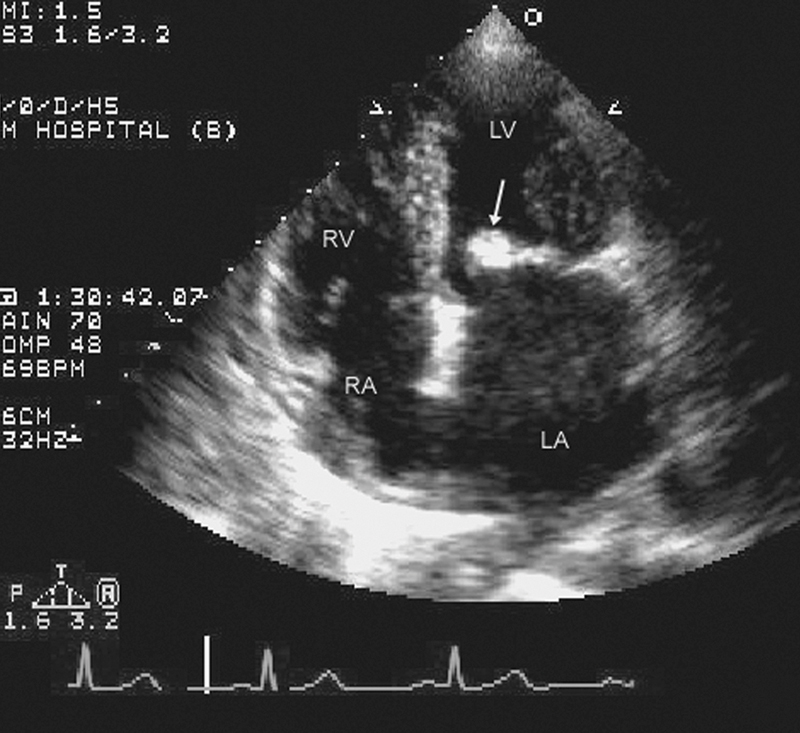

فحوصات تشخيصية لبعض امراض القلب والشرايين التاجية